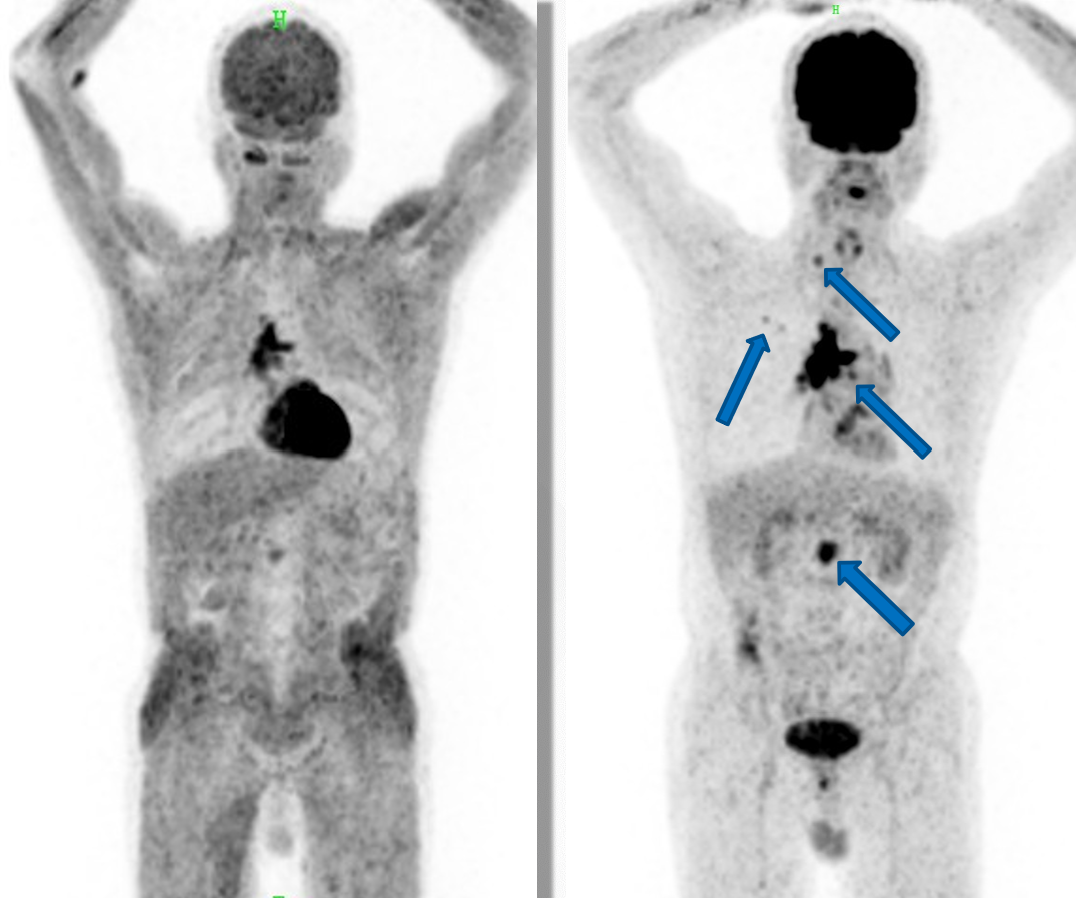

左图为检查前未禁食的图像,右图第二天空腹重做的图像,箭号所示为病灶。

在PET-CT检查中,18F-FDG是最为常用的显像剂,它就像葡萄糖的“孪生兄弟”,细胞分辨不出它和真正的葡萄糖,会一股脑儿地将它们摄取、运输进细胞。若在检查前进食高糖食物或者血糖水平过高,血液里就会有很多葡萄糖。这些葡萄糖和18F-FDG挤在细胞膜上的转运位点,争着被细胞“请”进去 ,形成了激烈的“竞争上岗”局面。

胰岛素是调节血糖的关键。血糖一高,胰岛素就大量分泌,它会把葡萄糖“领”进肌肉、脂肪等正常组织里,18F-FDG也跟着进去凑热闹。这样一来,肿瘤原本摄取18F-FDG发出的信号就被稀释,在PET-CT图像上,肿瘤和正常组织的对比度降低,医生很难一眼识别出肿瘤的位置和形态,很容易造成误诊或者漏诊。而且,PET-CT诊断依赖的SUV值,也会因为血糖高而增加诊断难度。